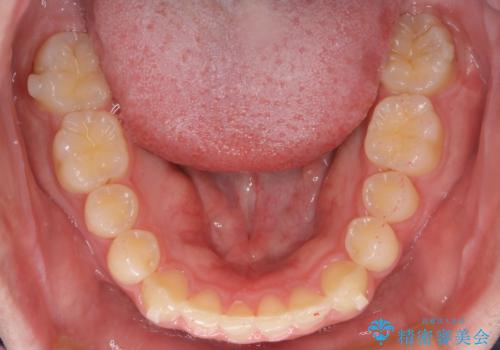

【インビザライン】前歯のガタガタと、前歯の噛み合わせが深いことを治したい。

- 前歯のガタガタと、前歯の噛み合わせが深いことを治したい。との主訴で来院されました。

シミュレーションを用いながら患者様と仕上がりについて相談しインビザラインにて治療を行いました。

仕上げは追加アライナーを数回利用しておこないました。